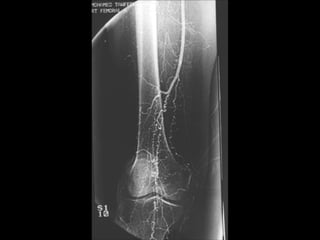

Observe

*Affection

from distal to

proximal.

*Pruning of

tibial vessels

and foot arch.

• 86.

• 88.